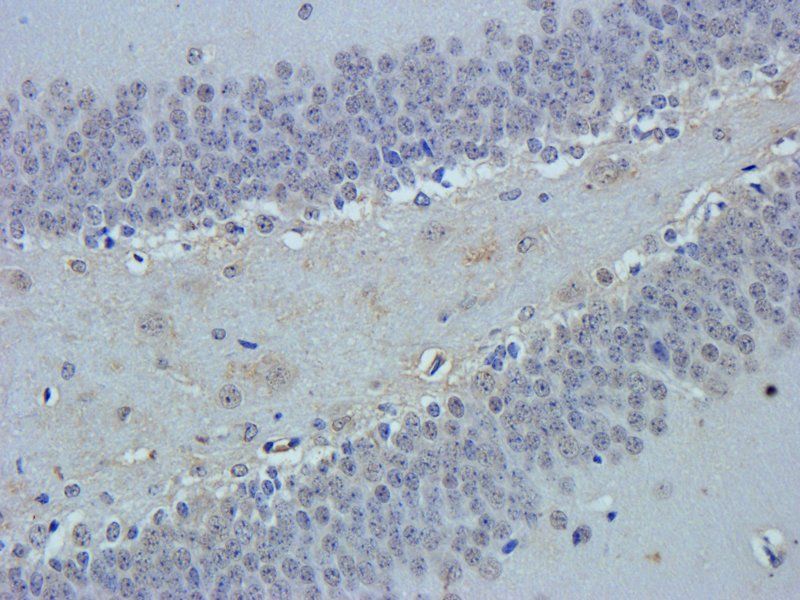

10 μg, 100 μg - Cubilin antibody [orb4997]Featured

ICC, IF, IHC-P, WB

Human, Mouse, Porcine, Rat

Rabbit

Polyclonal

Unconjugated